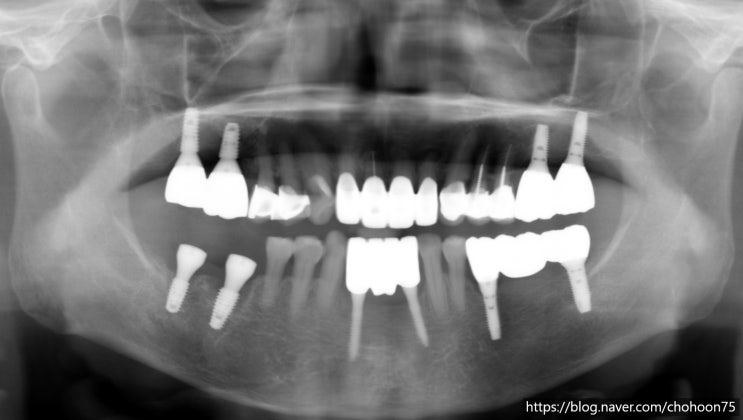

[조훈치과] 어금니 상실 부위 임플란트 식립 사례(7년 경과)

안녕하세요. 2024년 마지막 날 인사를 드립니다. 올 한 해는 어떻게 보내셨나요? 연초에 세웠던 계획과 다...